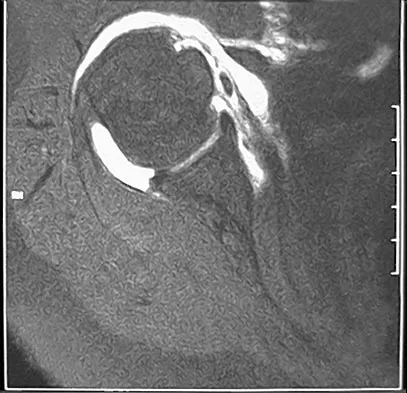

An MRI arthrogram of the elbow is shown in Figure 6. Based on these findings, what is the most likely diagnosis?

Explanation